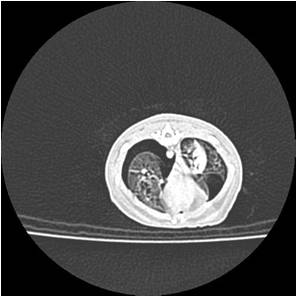

Lymphome des furets

Le lymphome est une tumeur des cellules blanches sanguines particulièrement fréquente chez le furet. Le lymphome du furet peut affecter le système digestif, les noeuds lymphatiques, le foie, la peau voire les yeux ou le système nerveux. C'est une maladie dont la présentation est très variée. Le diagnostic réclame des examens d'imagerie (radiographie, échographie, scanner, ponction de moelle osseuse) couplé à des analyses en laboratoire spécialisé (cytologie ou histologie). Les examens sont importants à plus d'un titre, d'une part pour évaluer l'extension de la maladie et d'autre part pour confirmer la maladie. En effet de nombreuses autres maladies (coronavirus notamment) peuvent ressembler au lymphome chez le furet.